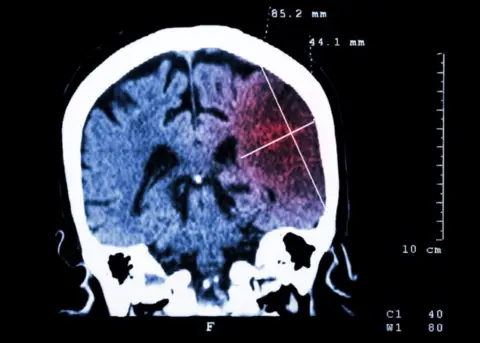

Little did Simon know, but the daily nosebleeds he'd been having were a sign that he had a genetic disorder called Hereditary Haemorrhagic Telangiectasia (HHT). This stops some blood vessels from developing properly and they build up with blood, known as arteriovenous malformations (AVMs). These AVMs were in Simon's brain where they ruptured, causing a haemorrhage and stroke.

Doctors have been keeping an eye out for further AVMs, the malformations which caused that initial hemorrhage. He has since had surgery to remove others - two craniotomies and a radiation beam - but it's a continual worry that more will develop.